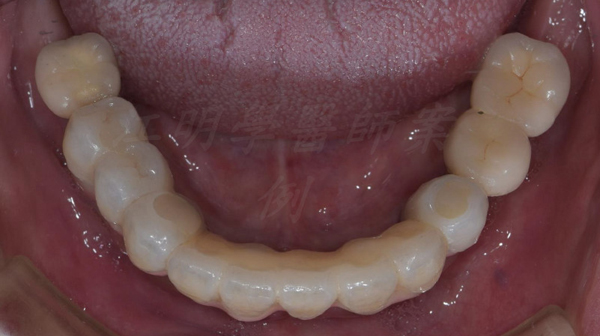

治療後

這些照片展示了您的牙齒在術後得到顯著改善,更加整齊、美觀,並達到理想的咬合狀態。